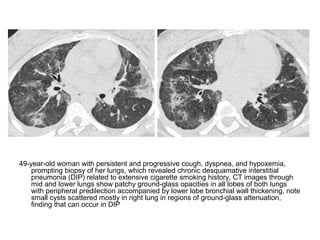

49-year-old woman with persistent and progressive cough, dyspnea, and hypoxemia,

prompting biopsy of her lungs, which revealed chronic desquamative interstitial

pneumonia (DIP) related to extensive cigarette smoking history, CT images through

mid and lower lungs show patchy ground-glass opacities in all lobes of both lungs

with peripheral predilection accompanied by lower lobe bronchial wall thickening, note

small cysts scattered mostly in right lung in regions of ground-glass attenuation,

finding that can occur in DIP